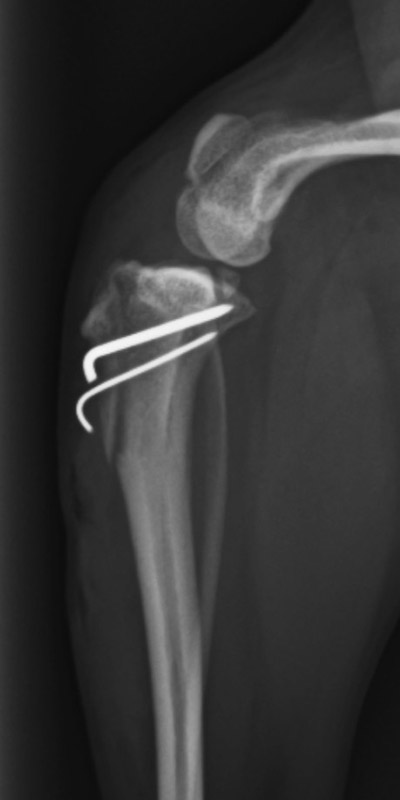

前十字靱帯断裂

柴犬(10歳)

持続する右後肢の挙上、疼痛

手術前

手術後